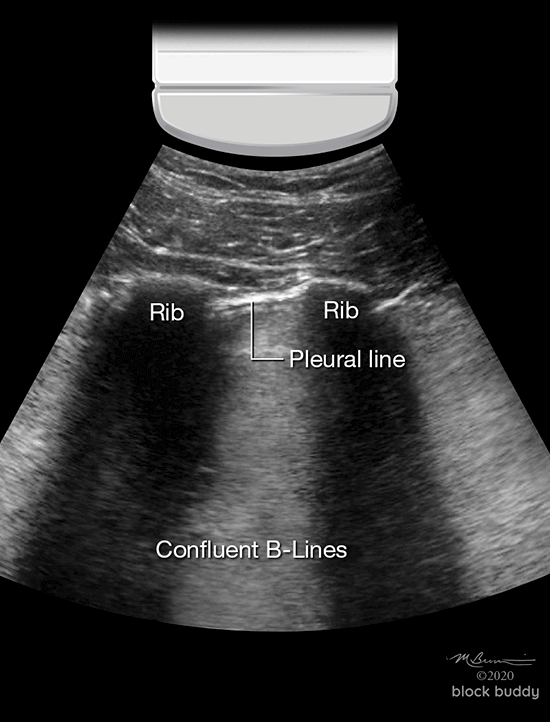

B-Lines

- Hyperechoic, vertical reverberation artifacts.

- Extend from the pleural line to the bottom of the screen.

- Obliterate A-lines.

- Move synchronously with lung sliding.

- Results from interlobular septal thickening (fluid) surrounded by air filled alveoli.

- This produces a significant acoustic impedance gradient, resulting in the reverberation artifacts.

- Most commonly seen in pulmonary edema (cardiogenic and non-cardiogenic).

- Also seen with interstitial pneumonia, acute respiratory distress syndrome (ARDS), pulmonary fibrosis, pulmonary contusion, atelectasis and malignancy.

- 2 or less B-lines between 2 ribs in any zone are a normal finding.

- 3 or more B-lines between ribs in any zone are pathologic.

- The presence of B-lines can be used to identify interstitial syndrome, but cannot distinguish between pulmonary edema, ARDS, or fibrosis.

- B-lines with lung sliding are indicative of pulmonary edema.

- B-lines without lung sliding, may indicate ARDS or pneumonia.

Pulmonary Edema

- Results from an increase of fluid in the lung interstitium.

- Lung sliding is present.

- 3 or more B-lines in at least 2 zones confirm the presence of pulmonary edema.

- Pulmonary edema is the most common cause of B-lines.

- As the severity of the edema progresses, multiple diffuse B-lines are produced.

- A hyperechoic confluent pattern (white out) between the ribs may occur as the B-lines fuse together.